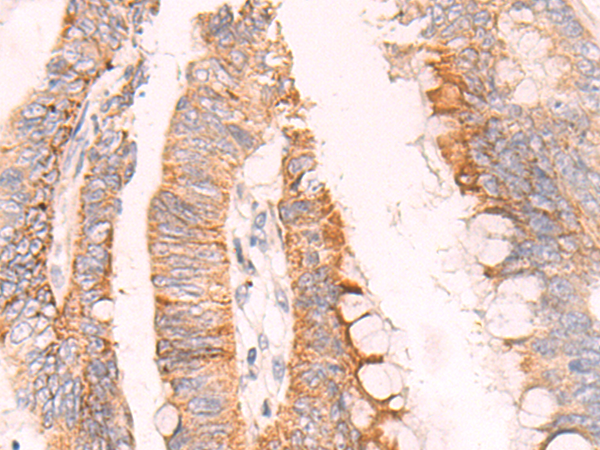

分类: 科研抗体货号: P04195别名: NBC2, NBC3, SBC2, NBCN1, SLC4A6应用: IHC反应种属: Human, Mouse, Rat